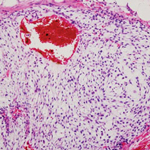

[16.09.2016] Острый лимфобластный лейкоз. Особенности роста раковых клеток

Группа ученых открыла новые перспективы в разработке эффективного лекарственного средства против агрессивной формы острого лимфобластного лейкоза (T-ALL). Был выявлен новый молекулярный механизм, который увеличивает жизнеспособность раковых Т-клеток и способствует их размножению.

Раковые клетки используют специальный сигнальный путь для поддержки интенсивного кислородного обмена и способности к делению. Сигнальный путь работает на основе белка ORP4L. Этот белок активно воспроизводится только раковыми Т-клетками и никогда не встречается в здоровых лейкоцитах